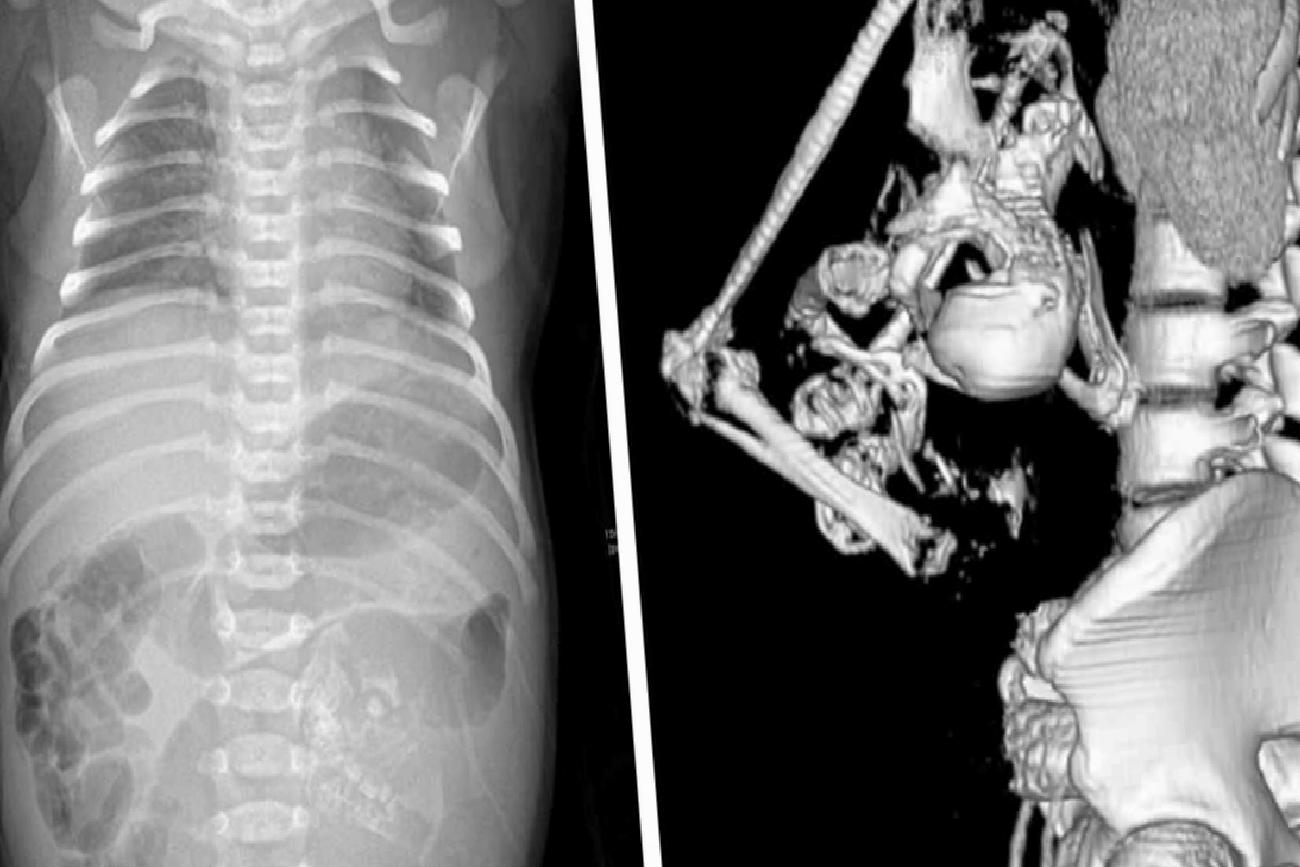

Nadir de olsa benzer bir vakaya daha önce rastlanmıştı. Geçtiğimiz yıl Çin’de, 1 yaşındaki bir kız çocuğunun motor becerilerinde gerilik şikayeti ile hastaneye getirilen ailesi, kızlarının kafatasında gelişmemiş ikiz kardeşinin fetüsü ile doğduğunu öğrendi. Ne yazık ki, bu durumda 1 yaşındaki bebek ameliyata alındı ancak hayatını kaybetti.

Bilimsel literatürde ‘Fetus in fetu’ olarak adlandırılan bu durumun benzerlerine oldukça nadir rastlandığını belirten uzmanlar, geçmişte kaydedilen benzer vakaların sayısının 200 civarında olduğunu ifade ediyorlar. Bu tür durumların tıbbi açıdan incelenmesi ve anlaşılması, sağlık bilimleri alanında önemli bir gereklilik olarak öne çıkıyor.